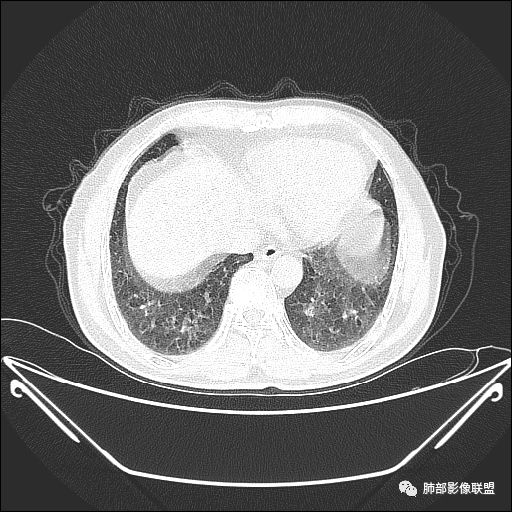

住院4天后行胸部增强CT

吴婧老师和南边老师都对该病例进行了深入分析。从支气管管壁的增厚,支气管狭窄后扩张,支气管粘液栓,病灶形态,到病灶不均匀强化及坏死彻底,到周边病灶及肺组织空气的潴留,加之纵隔内淋巴结肿大伴钙化等等,都支持慢性炎性病灶,尤其是结核。

墨西哥仙人掌征---结核        影像上结核灶,粗大的均匀枝干,推测是支气管囊状扩张引起的,在非支气管区,形成圆形坏死囊群;如果这些坏死比较稀薄,又遇到扩张支气管,就会形成粗大的“墨西哥仙人掌”。结核引起的支气管近端炎症纤维化,可以造成支气管阻塞,从而将干酪样坏死物封堵在管腔内。仙人掌主干内部应该是干酪为主,稀薄的,具有流动性,时间久了会出现钙化。

结核坏死与鳞癌鉴别有一点是结核坏死没有方向性,鳞癌有。鳞癌靠近支气管近端部分,血供容易维持,不易坏死,所以坏死靠外侧。而结核干酪样坏死,把一定体积的流动性坏死物,包裹起来,什么形状最省料?坏死物包裹,表面积最省的自然是圆球形,而遇到支气管,坏死物一多,就把支气管撑大了。包裹物是就地取材,扩张的支气管就成了包裹结构。